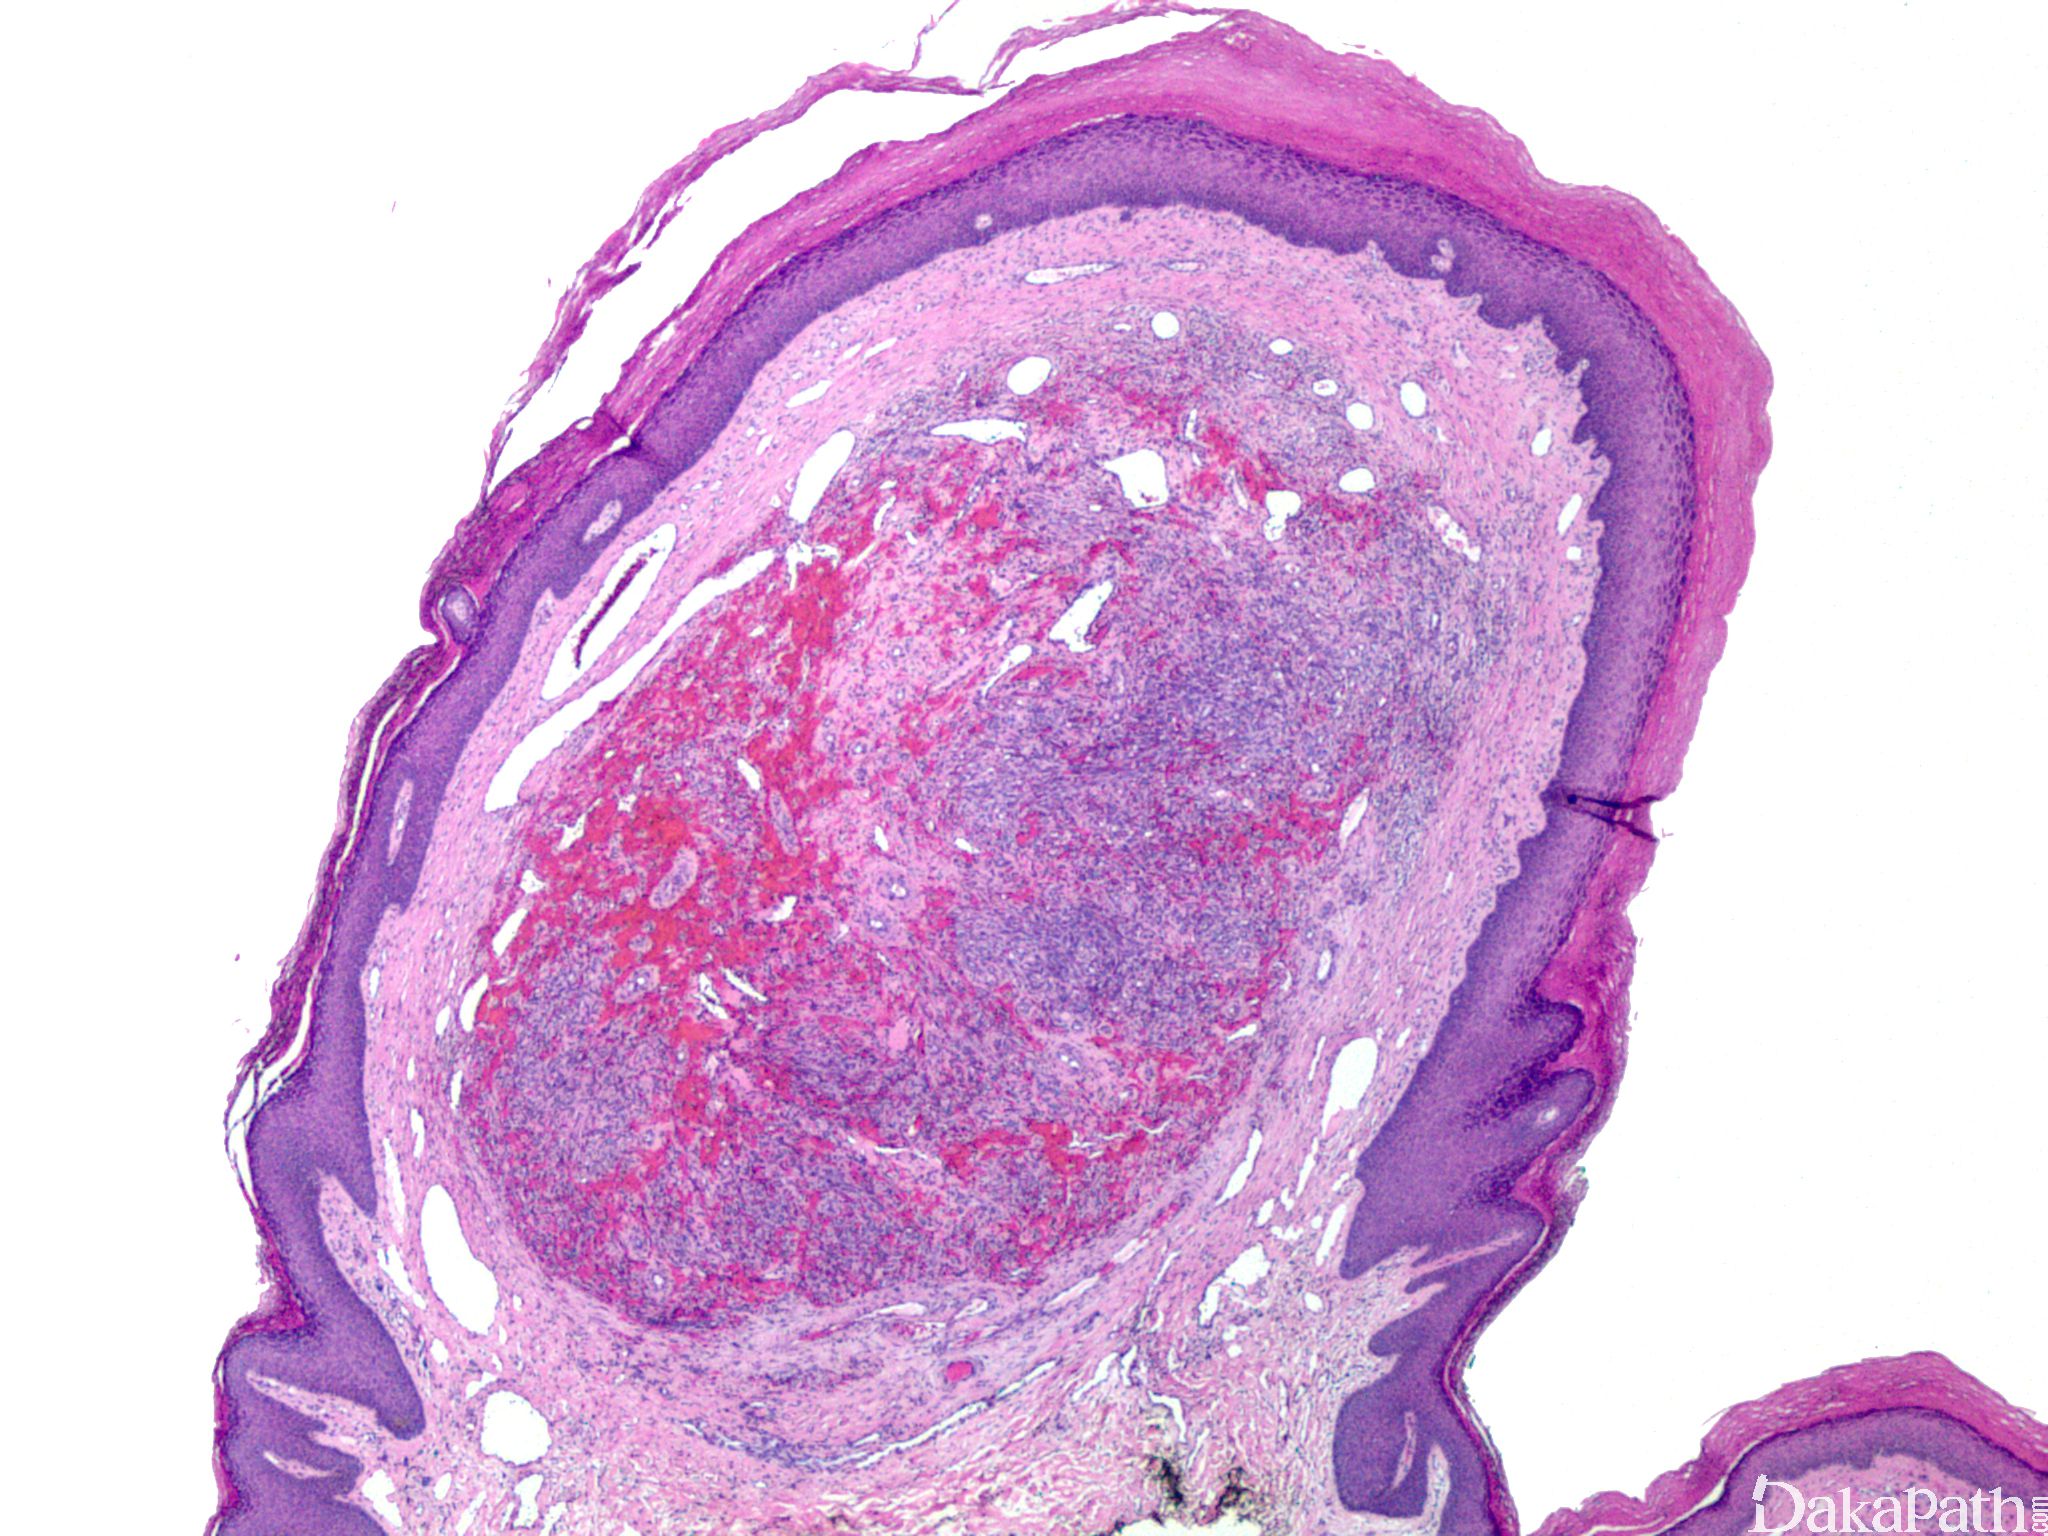

典型的卡波西肉瘤细胞无明显的异型性,核分裂像也不多见,但少数病例中瘤细胞分化较差,异型性明显,可见较多的核分裂像。依据病变进展分为四期:

IV 期为结节期:结节期的病变边界清楚,主要由网状或裂隙状的毛细血管及其周围纵横交错的嗜酸性梭形细胞组成,梭形细胞有一定异型性,核分裂偶见;梭形细胞和血管之间为含有红细胞的裂隙,横切面呈筛孔状或蜂窝状,在梭形细胞内或细胞外可见抗淀粉酶消化 PAS 阳性的嗜伊红色透明小体,结节的边缘常见炎症细胞浸润、含铁血黄素沉着和扩张的血管。 典型的卡波西肉瘤细胞无明显的异型性,核分裂像也不多见,但少数病例中瘤细胞分化较差,异型性明显,可见较多的核分裂像。